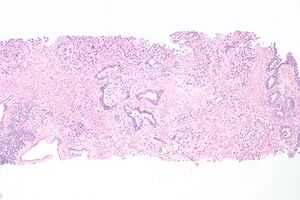

Microanatomy

The cells lining the urethra (the epithelium) start off as transitional cells as it exits the bladder, which are variable layers of flat to cuboidal cells that change shape depending on whether they are compressed by the contents of the urethra.[12] Further along the urethra there are pseudostratified columnar and stratified columnar epithelia.[12] The lining becomes multiple layers of flat cells near the end of the urethra, which is the same as the external skin around it.[12]

There are small mucus-secreting urethral glands, as well as bulbo-urethral glands of Cowper, that secrete mucous acting to lubricate the urethra.[12]

The urethra consists of three coats: muscular, erectile, and mucous, the muscular layer being a continuation of that of the bladder.